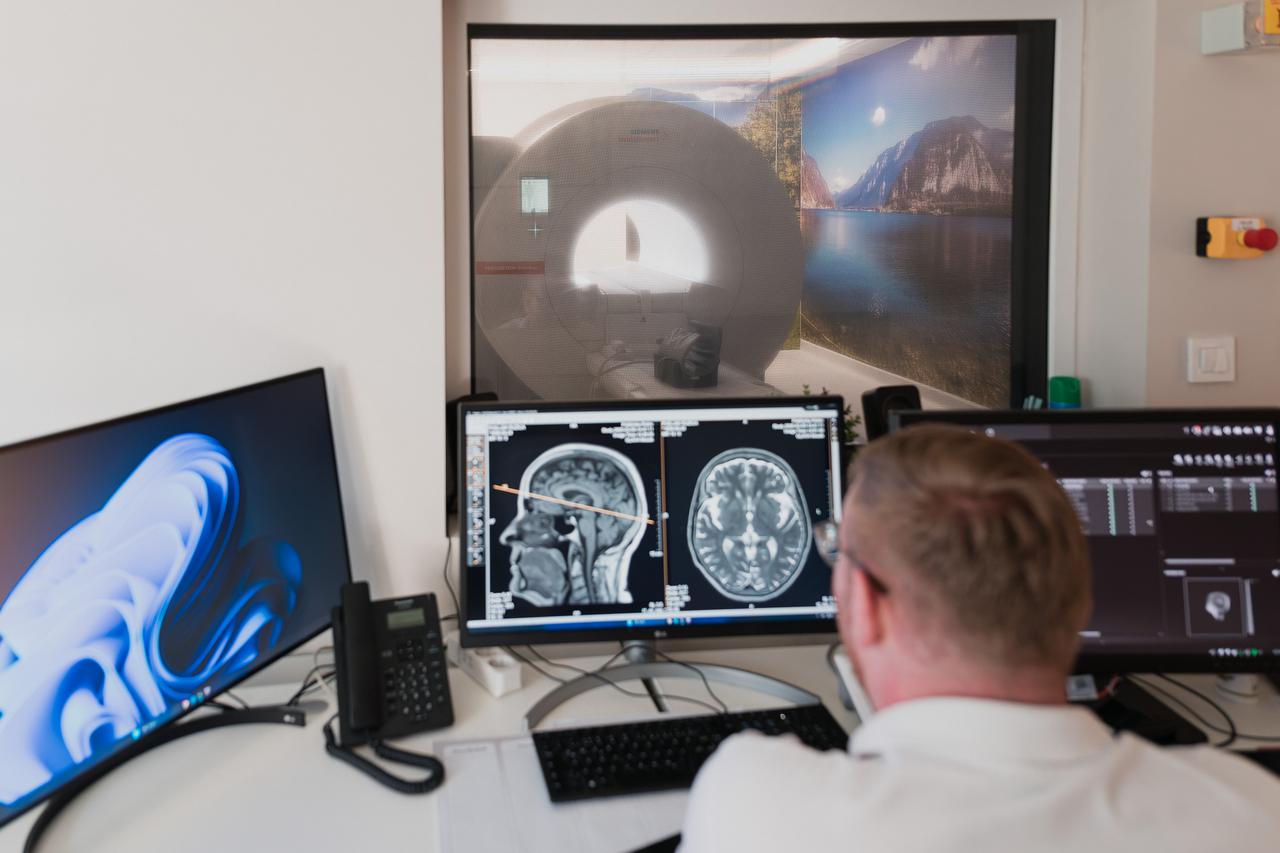

Na rendgenu prije operacije otkriveno je koliko zubi ima dječak, a izgledali su kao napunjena vrećica. Zapravo je u ustima imao benigni tumor, a nije poznato je li on uzrokovan genima ili okolinom.

Ovo je toliko rijetki slučaj da su liječnici morali sve zabilježiti fotoaparatom, a sličan slučaj dogodio se 2014. godine u Mumbaiju kada su iz usta 17-godišnjaka izvadili 232 zuba.